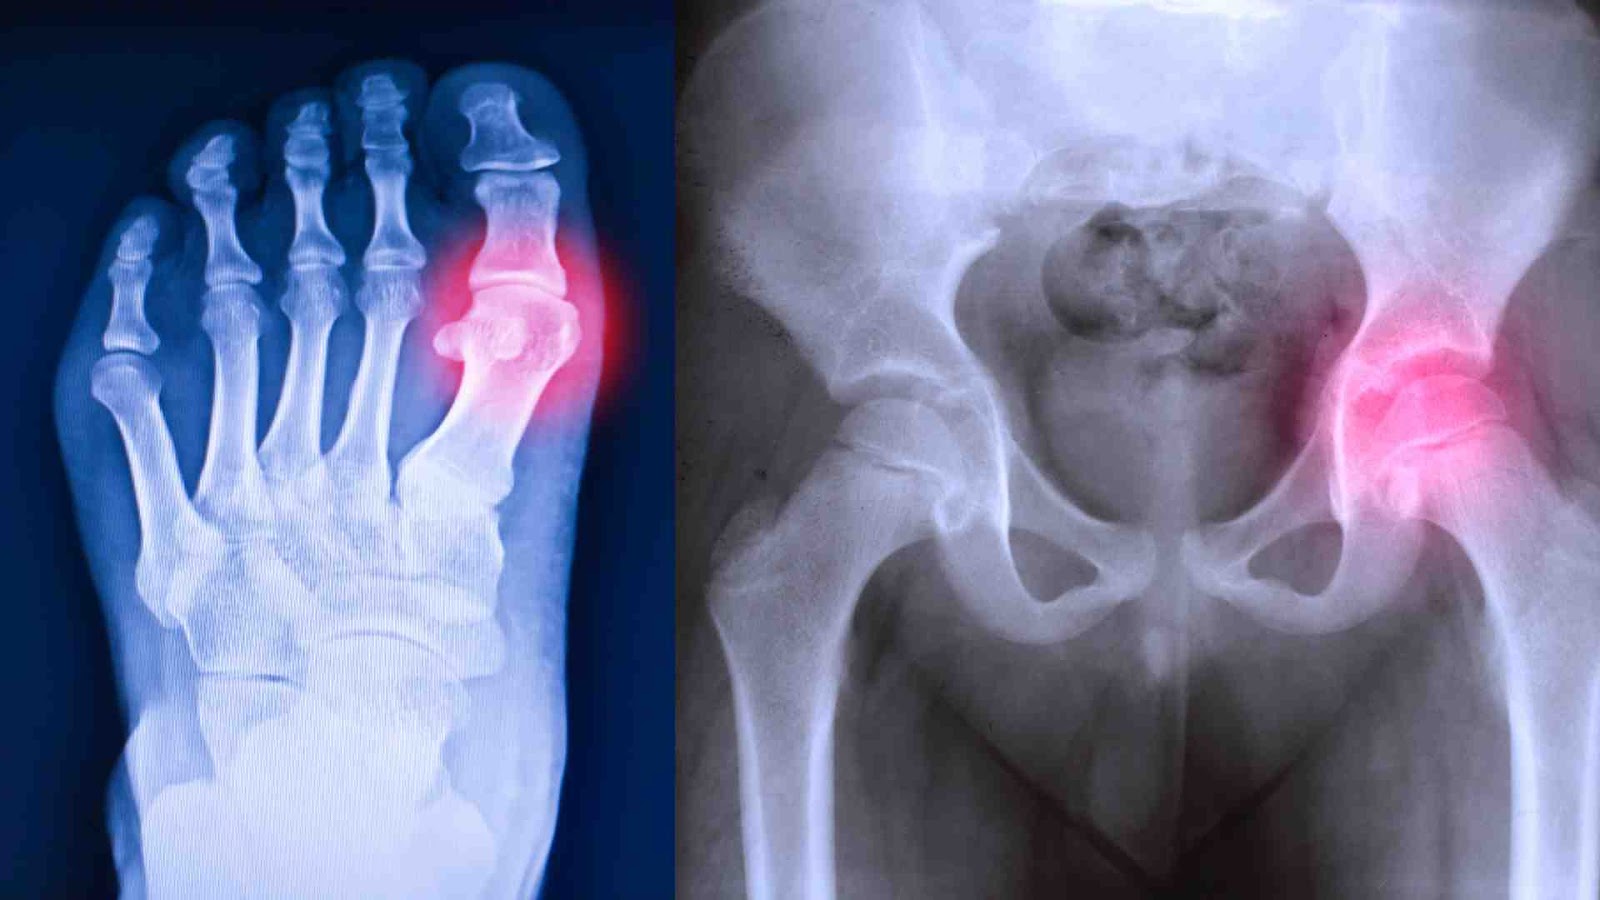

One in 5 Australians over the age of 45 has osteoarthritis. The latest science reveals inflammation causes the pain, not wear and tear on the joints. Paula Goodyer explains the best way to tackle it.

Let’s reboot our thinking about osteoarthritis - it’s less about ‘wear and tear’ on our joints and cartilage and more about inflammation.

If you’re feeling pain or stiffness in your hands, big toe, knees or hips or wondering why your joints make clicking noises, feel like they grate or have become inflexible, then it’s worth a trip to the doctor..